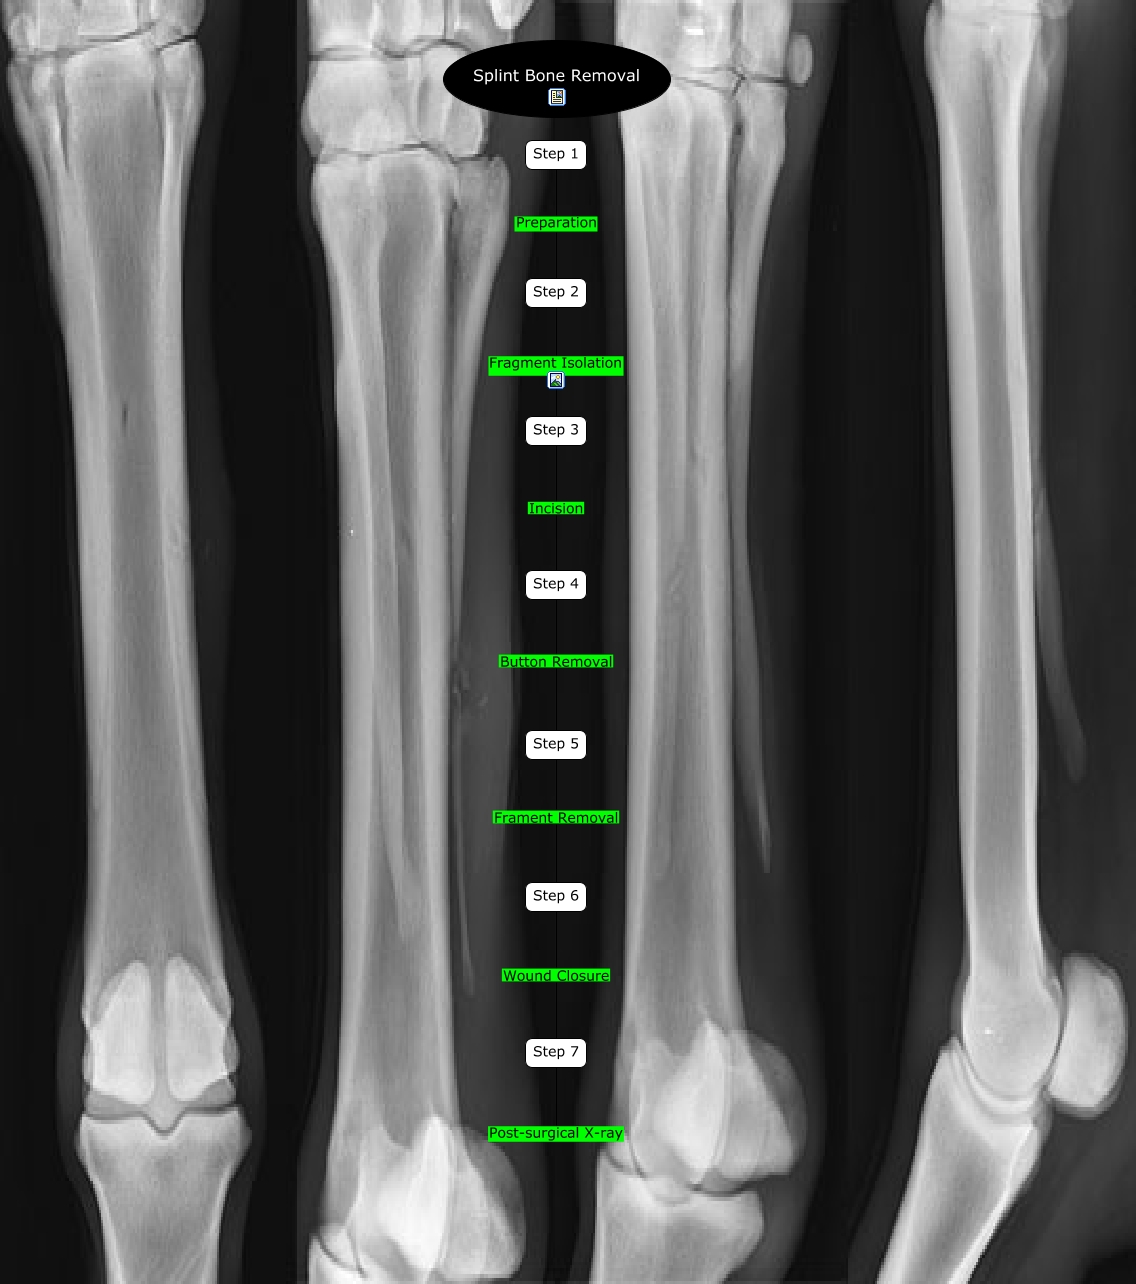

Splint Bone Removal Splint Bone Fracture Surgery Cost +65 6250 0000 (orchard) or +65 6898 6898 (novena) for appointment bookings, please whatsapp. Fractures of metacarpal and metatarsal ii and iv (the splint bones) were treated in 283 horses over an 11 year period. for enquiries, please call. Fractures that require surgery may include: orthopaedic surgeon fixing broken bone. In 21 cases the proximal portion of the. Splint Bone Fracture Surgery Cost.

Splint Bone Removal Splint Bone Fracture Surgery Cost Splints and casts support and protect injured bones and soft tissue,. Fractures that require surgery may include: Bone that has broken into several pieces (‘comminuted’) fracture that has moved. orthopaedic surgeon fixing broken bone. You might need a cast after other injuries or some types of. A bone fracture is a medical condition in which a bone is cracked. Splint Bone Fracture Surgery Cost.